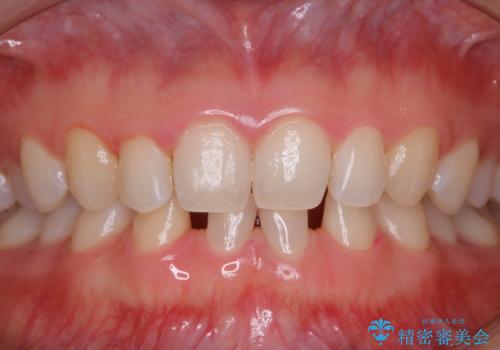

- すき間の部分の歯磨きがしずらく、クリーニング希望で来院されました。今後はセラミックによる治療を考えてとの事でした。PMTC(保険外治療)30分コースを行いました。

PMTC(保険外治療)とは、歯垢・歯石・着色などを除去することです。磨きのこしなどにより歯垢が付着し続けると、歯石に変化していきます。歯石になってしまったら、歯ブラシだけで落とすことができなくなります。そのため歯科医院での専門的な機械・材料を使用してのクリーニングが必要です。